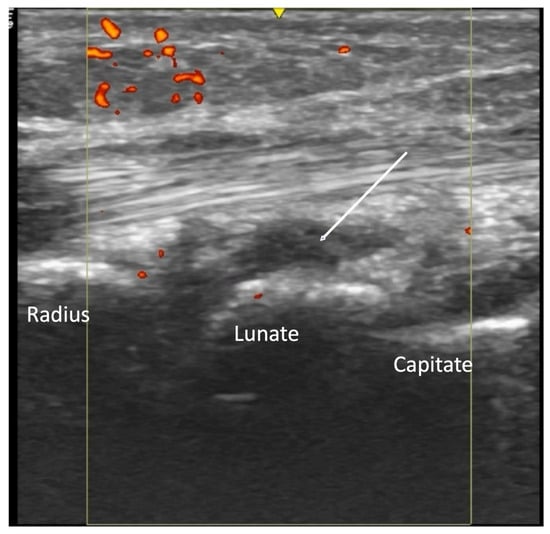

4.2. Evaluation of the Wrist

4.2.2. Volar Aspect